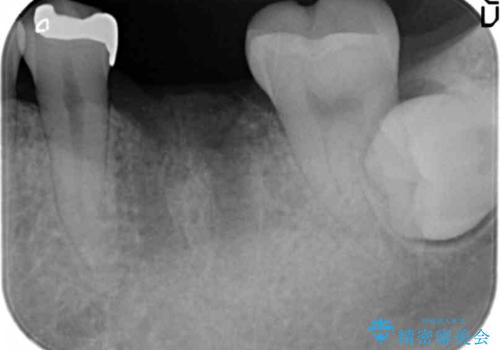

銀歯を除去して見ると内部で虫歯が再発し、歯の辺縁は破折し保存が難しく抜歯をしなければいけない状態でした。

抜歯後ブリッジとインプラント治療を検討・相談し、より周囲の歯を削らずに済むインプラント治療を希望されたのでインプラントによる機能回復を計画します。